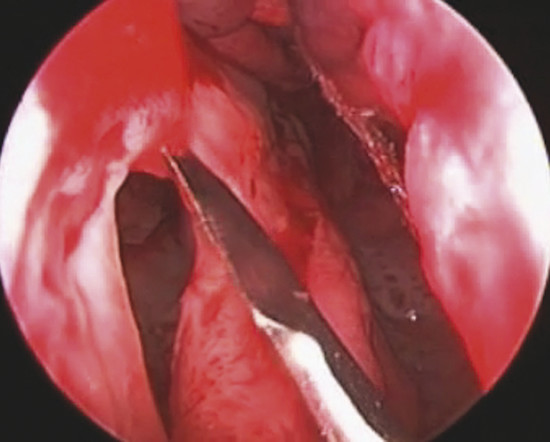

On the other side, in oval perforation with horizontal major diameter, a horizontal incision as long as the perforation major diameter is performed by a sickle knife on nasal mucosa 1 cm to the dorsal border of septal cartilage. The mucoperichondrial flap is then elevated from the perforation margin up to the incision. The flap is thus transposed downward and the borders of the perforation are sutured together with a 3–0 Vicryl suture (Fig. 19‑3).

In the case of rounded perforations, a rotation/advancement mucoperiosteal flap is designed by a rounded incision based posteriorly on the nasal-septal artery and elevated up to 1 cm from the choana (Fig. 19‑4). Also, in this case the flap is rotated to reach the inferior border of the perforation and sutured with a 3–0 Vicryl suture (Fig. 19‑5).